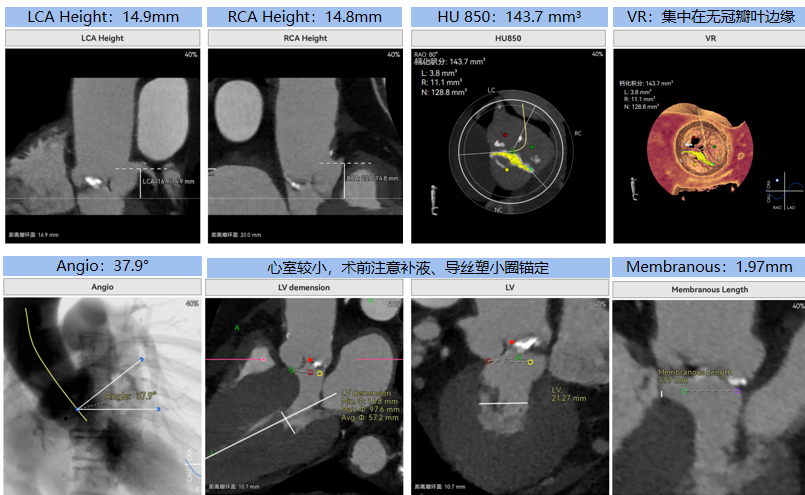

病例概览

患者病史 男性,74y, 因 “发现心脏瓣膜病 1 年,加重伴喘气半年” 入院。门诊检查显示主动脉瓣重度AS并伴轻-中度AR。患者基础疾病较多:胸腹主动脉多发穿透性溃疡、心功能III级等,手术指征明确,但风险极高。 术前CT LVOT- Annulus 倒梯形,对植入瓣膜有挤压位移风险,Annulus直径23.7mm,瓣叶增厚,钙化集中在无冠窦边缘。 左冠脉开口高度可,瓣叶不长、窦部空间较大,无冠脉风险;室间隔膜部较短,有一定PPI风险,心脏角度37.9°;心室较小,有一定循环崩溃风险,术前注意补液。 术前造影角度及入路:血管入路散在钙化、无迂曲;主动脉弓条件好、双侧股动脉直径大、右股穿刺点侧壁存在环形钙化 左右重合位:RAO 7° CAU 21° 右窦中心位:LAO2 1° CAU 1° 手术策略 20mm球囊预扩后植入AV26瓣膜,同时做好预防循环崩溃、传导阻滞的应急预案。 术中挑战 1)球囊预扩:20mm球囊预扩时无明显 “腰征”,但存在少量反流,提示瓣膜钙化与解剖结构对扩张的阻力不均 2)首次释放偏差:第一次定位释放时,瓣膜在 “开花” 过程中下滑约 3mm,工作位观察显示小弯侧瓣周漏较多(深度超过完全覆膜区),需二次调整。 3)二次精准定位:以猪尾导管为参照,将定位点调整至 “猪尾 - 2mm” 处,结合真实窦底深度(较深)重新释放,最终瓣膜位置稳定,瓣周漏显著减少。 术后即刻效果: 瓣膜形态良好,跨瓣压差从术前的 67mmHg 降至 6mmHg,且无明显瓣周漏,冠脉开口通畅; Commisural Alignment 术后即刻超声: Prostyle A®预装干瓣——助力临床最优化解决方案: √ 平衡的径向支撑力:特殊的解剖结构下位置形态良好,术后跨瓣压差大幅降低,血流动力学改善明显; √ 80%可回收设计:支持术中二次调整释放位置,保证精准释放; √ 平衡的收腰设计&Commissural Alignment设计: 为患者后期冠脉PCI保留了生命通道;